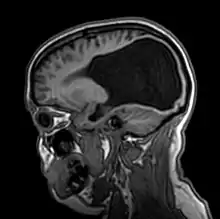

Colpocephaly is a cephalic disorder involving the disproportionate enlargement of the occipital horns of the lateral ventricles and is usually diagnosed early after birth due to seizures. It is a nonspecific finding and is associated with multiple neurological syndromes, including agenesis of the corpus callosum, Chiari malformation, lissencephaly, and microcephaly.[1] Although the exact cause of colpocephaly is not known yet, it is commonly believed to occur as a result of neuronal migration disorders during early brain development, intrauterine disturbances, perinatal injuries, and other central nervous system disorders.[2] Individuals with colpocephaly have various degrees of motor disabilities, visual defects, spasticity, and moderate to severe intellectual disability.[3] No specific treatment for colpocephaly exists, but patients may undergo certain treatments to improve their motor function or intellectual disability.

Colpocephaly is characterized by disproportionately large occipital horns of the lateral ventricles (also frontal and temporal ventricles in some cases). MRI and CT scans of patients demonstrate abnormally thick gray matter with thin poorly myelinated white matter. This happens as a result of partial or complete absence of the corpus callosum. Corpus callosum is the band of white matter connecting the two cerebral hemispheres. The corpus callosum plays an extremely important role in interhemispheric communication, thus lack of or absence of these neural fibers results in a number of disabilities.[12]

After birth, MR imaging can be done to look for cephalic abnormalities. This is the most commonly used method for diagnosing colpocephaly. Physicians look for abnormally large occipital horns of the lateral ventricles and diminished thickness of white matter.[12] Spinal tapping is not a preferred method for diagnosis because newborn babies with colpocephaly or hydrocephaly have open fontanelles which makes it difficult to collect CSF. Also, colpocephaly is not associated with increased pressure.[13]